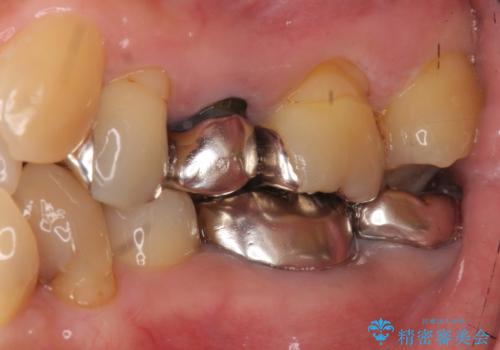

- 八重歯の矯正を希望されて来院。

歯は入りきらないため、通常の抜歯矯正を行いました。

歯がご年齢的に動きにくいため、被せ物のやり替えを含めて治療期間の短縮を図りました。

矯正治療自体は2年半、虫歯治療等で1年ほどかかっています。